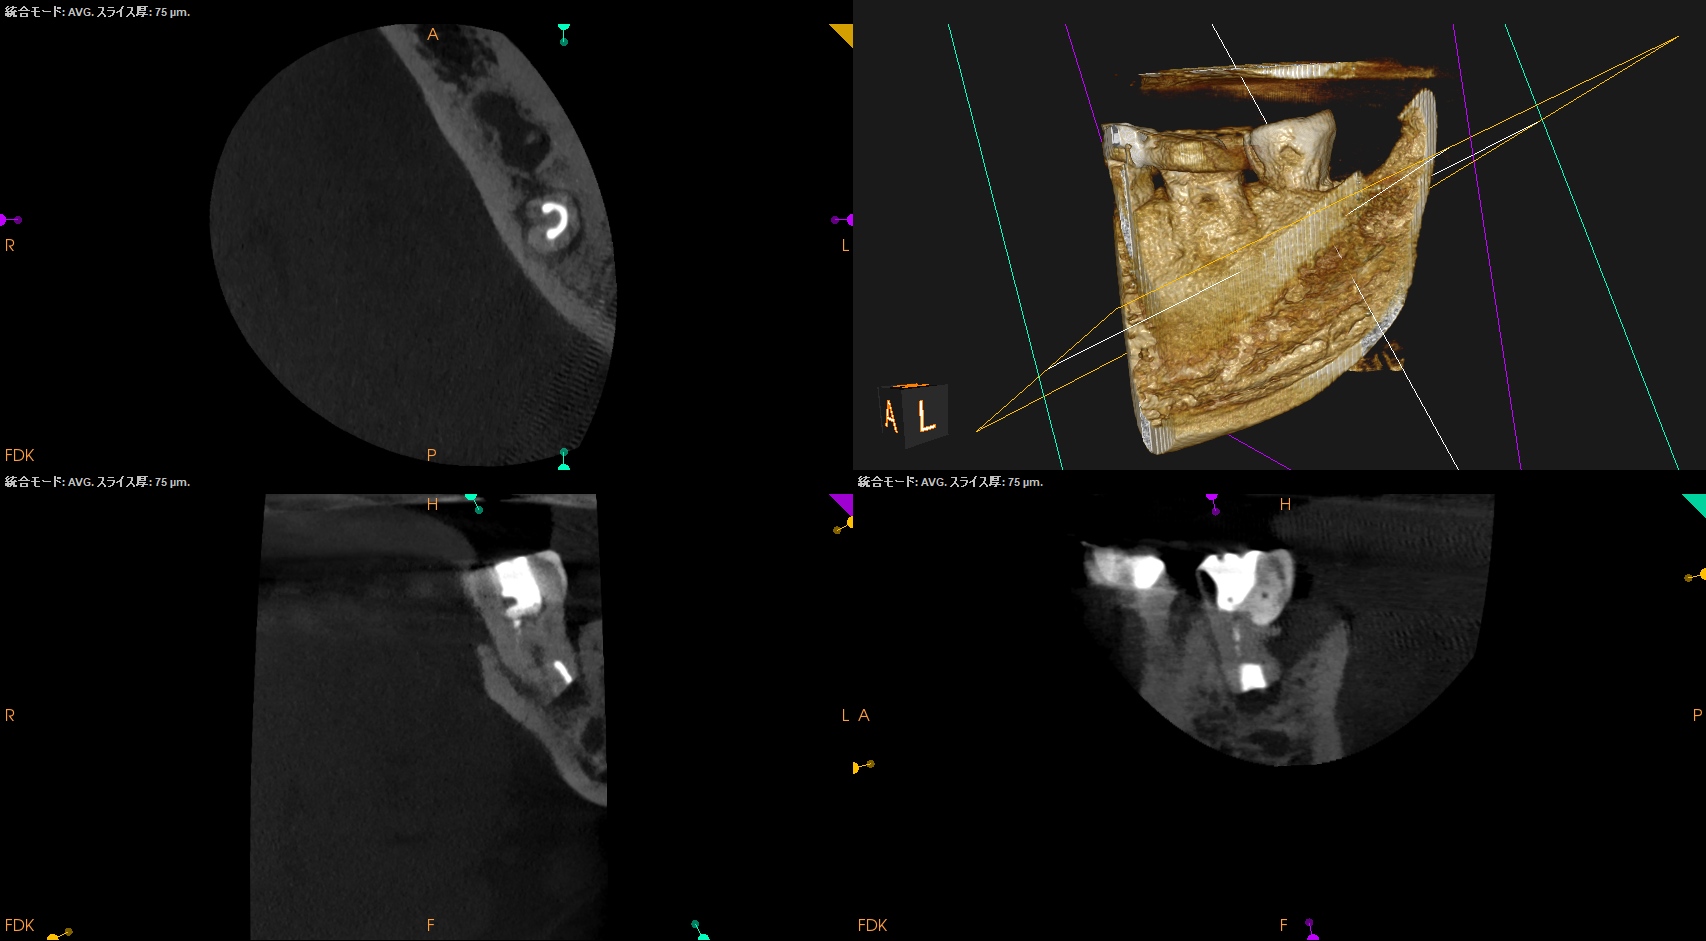

CBCT(2025.12.10)

ML

MB

D

遠心方向から見ると、

絶望的な状態であることがわかる。

抜歯し、口腔外で虫歯を除去し、Apicoectomyして抜歯窩へ戻すIntentional Replantationを行う必要があるだろう。